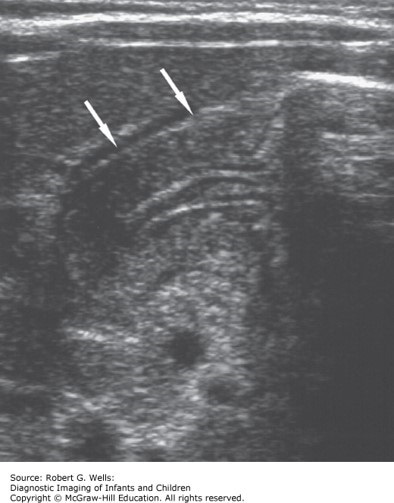

The correct answer is “B.” IHPS occurs in approximately 2 to 3.5 newborns per 1000 live births. It is more common in males than females (4:1 to 6:1) and in premature infants. It may run in families. Approximately 30% of cases occur in first-born children (approximately 1.8-fold increased risk). The etiology is unknown. Symptoms usually begin between 3 and 5 weeks of age, and very rarely occur after 12 weeks of age. Vomiting in IHPS is typically forceful and nonbilious, and tends to occur immediately after feeding. The force and timing can help to distinguish IHPS from physiologic gastroesophageal reflux, in which most episodes of vomiting are not forceful and may occur 10 minutes or more after the meal. A history of bilious vomiting does not exclude IHPS but should raise concern about more distal intestinal obstruction, such as malrotation with volvulus or Hirschsprung disease. Vascular rings typically have associated respiratory symptoms such as stridor. Option “E” is incorrect as the case clearly says the newborn is breastfed. Here’s a tip if you missed that: slow down, speedy reader! IHPS is diagnosed by ultrasound and treated surgically after rehydration and correction of electrolyte abnormalities.

Photo: Chapter 35 The Stomach, Wells RG. Diagnostic Imaging of Infants and Children; 2015.